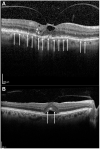

Purpose: To assess generalized (GD) and focal ellipsoid zone disruption (FD) in patients with symptomatic vitreomacular adhesion (sVMA) using spectral domain optical coherence tomography (SD-OCT) following ocriplasmin.

Patients and methods: OZONE was a Phase 4, retrospective study of patients with sVMA treated with a single intravitreal injection of ocriplasmin (0.125 mg). Data from adult patients with at least 6-month follow-up after ocriplasmin were included. SD-OCT was performed at baseline (within 30 days before ocriplasmin), before Day 21 post-injection (early observation, EO), and by last observation (LO) which was maximally 6 months post-injection. The main outcome measure was the development of new and the evolution of existing FD/GD at EO and LO.

Results: The study enrolled 134 eyes/patients from 22 sites in the USA. At baseline, 87 eyes (64.9%) had FD, 21 eyes (15.7%) had GD and 26 eyes (19.4%) had no FD/GD. Among the eyes without FD/GD at baseline, 13 (50%) and 8 (30.8%) developed FD or GD, respectively, by EO. By LO, FD/GD improvement or resolution was seen in >80% of these eyes. Among the eyes with FD/GD at baseline, <40% had improving/resolving EZ integrity at LO. The absence of FD/GD at baseline was associated with less persistent FD/GD at LO (P<0.0005). The presence of FD with MH at baseline was associated with persistent FD at LO (P=0.027).

Conclusion: The fact that a large majority of eyes had FD/GD prior to ocriplasmin was unexpected and demonstrates that EZ disruptions are common in sVMA. This suggests that loss of EZ integrity may be part of the natural history of this disorder. It is hypothesized that the status of the EZ at baseline is a contributing, ocriplasmin independent modulator of subsequent EZ changes after ocriplasmin. Prospective analyses which include a sham control group would be required to test this hypothesis.